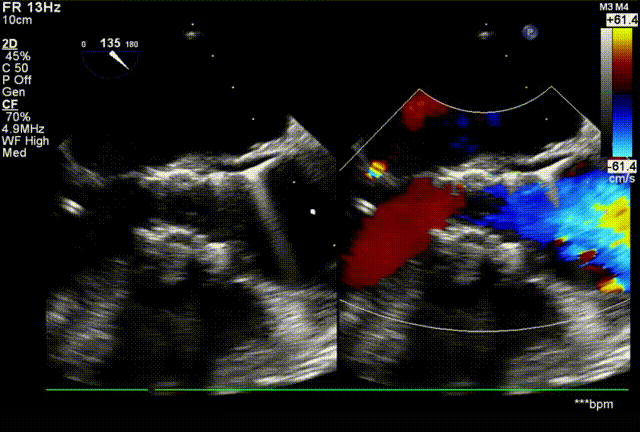

患者老年男性,83岁,10余年前劳累后出现胸闷,气短,休息后症状缓解,一周前患者症状加重,入院超声检查显示主动脉瓣重度狭窄,可见多发强回声钙化,较大者约1.1*0.7cm,开放明显受限,闭合尚可,峰值流速5.19m/s,平均压差68mmHg,室间隔及左室壁增厚。

起搏150次/分,TaurusElite AV26瓣膜高位快速释放了四分之三,评估冠脉血流良好,无阻挡,瓣膜位置合适,释放后,造影显示反流增加,超声显示瓣周漏主要存在左右钙化嵴处,前向流速明显减小,跨瓣压差由术前60 mmHg减小到20mmHg,瓣膜横截面最大处18mm。

术后超声显示,瓣膜与主动脉贴合更好,但是在左右钙化嵴处还是存在少中量反流。

术后即刻超声评估